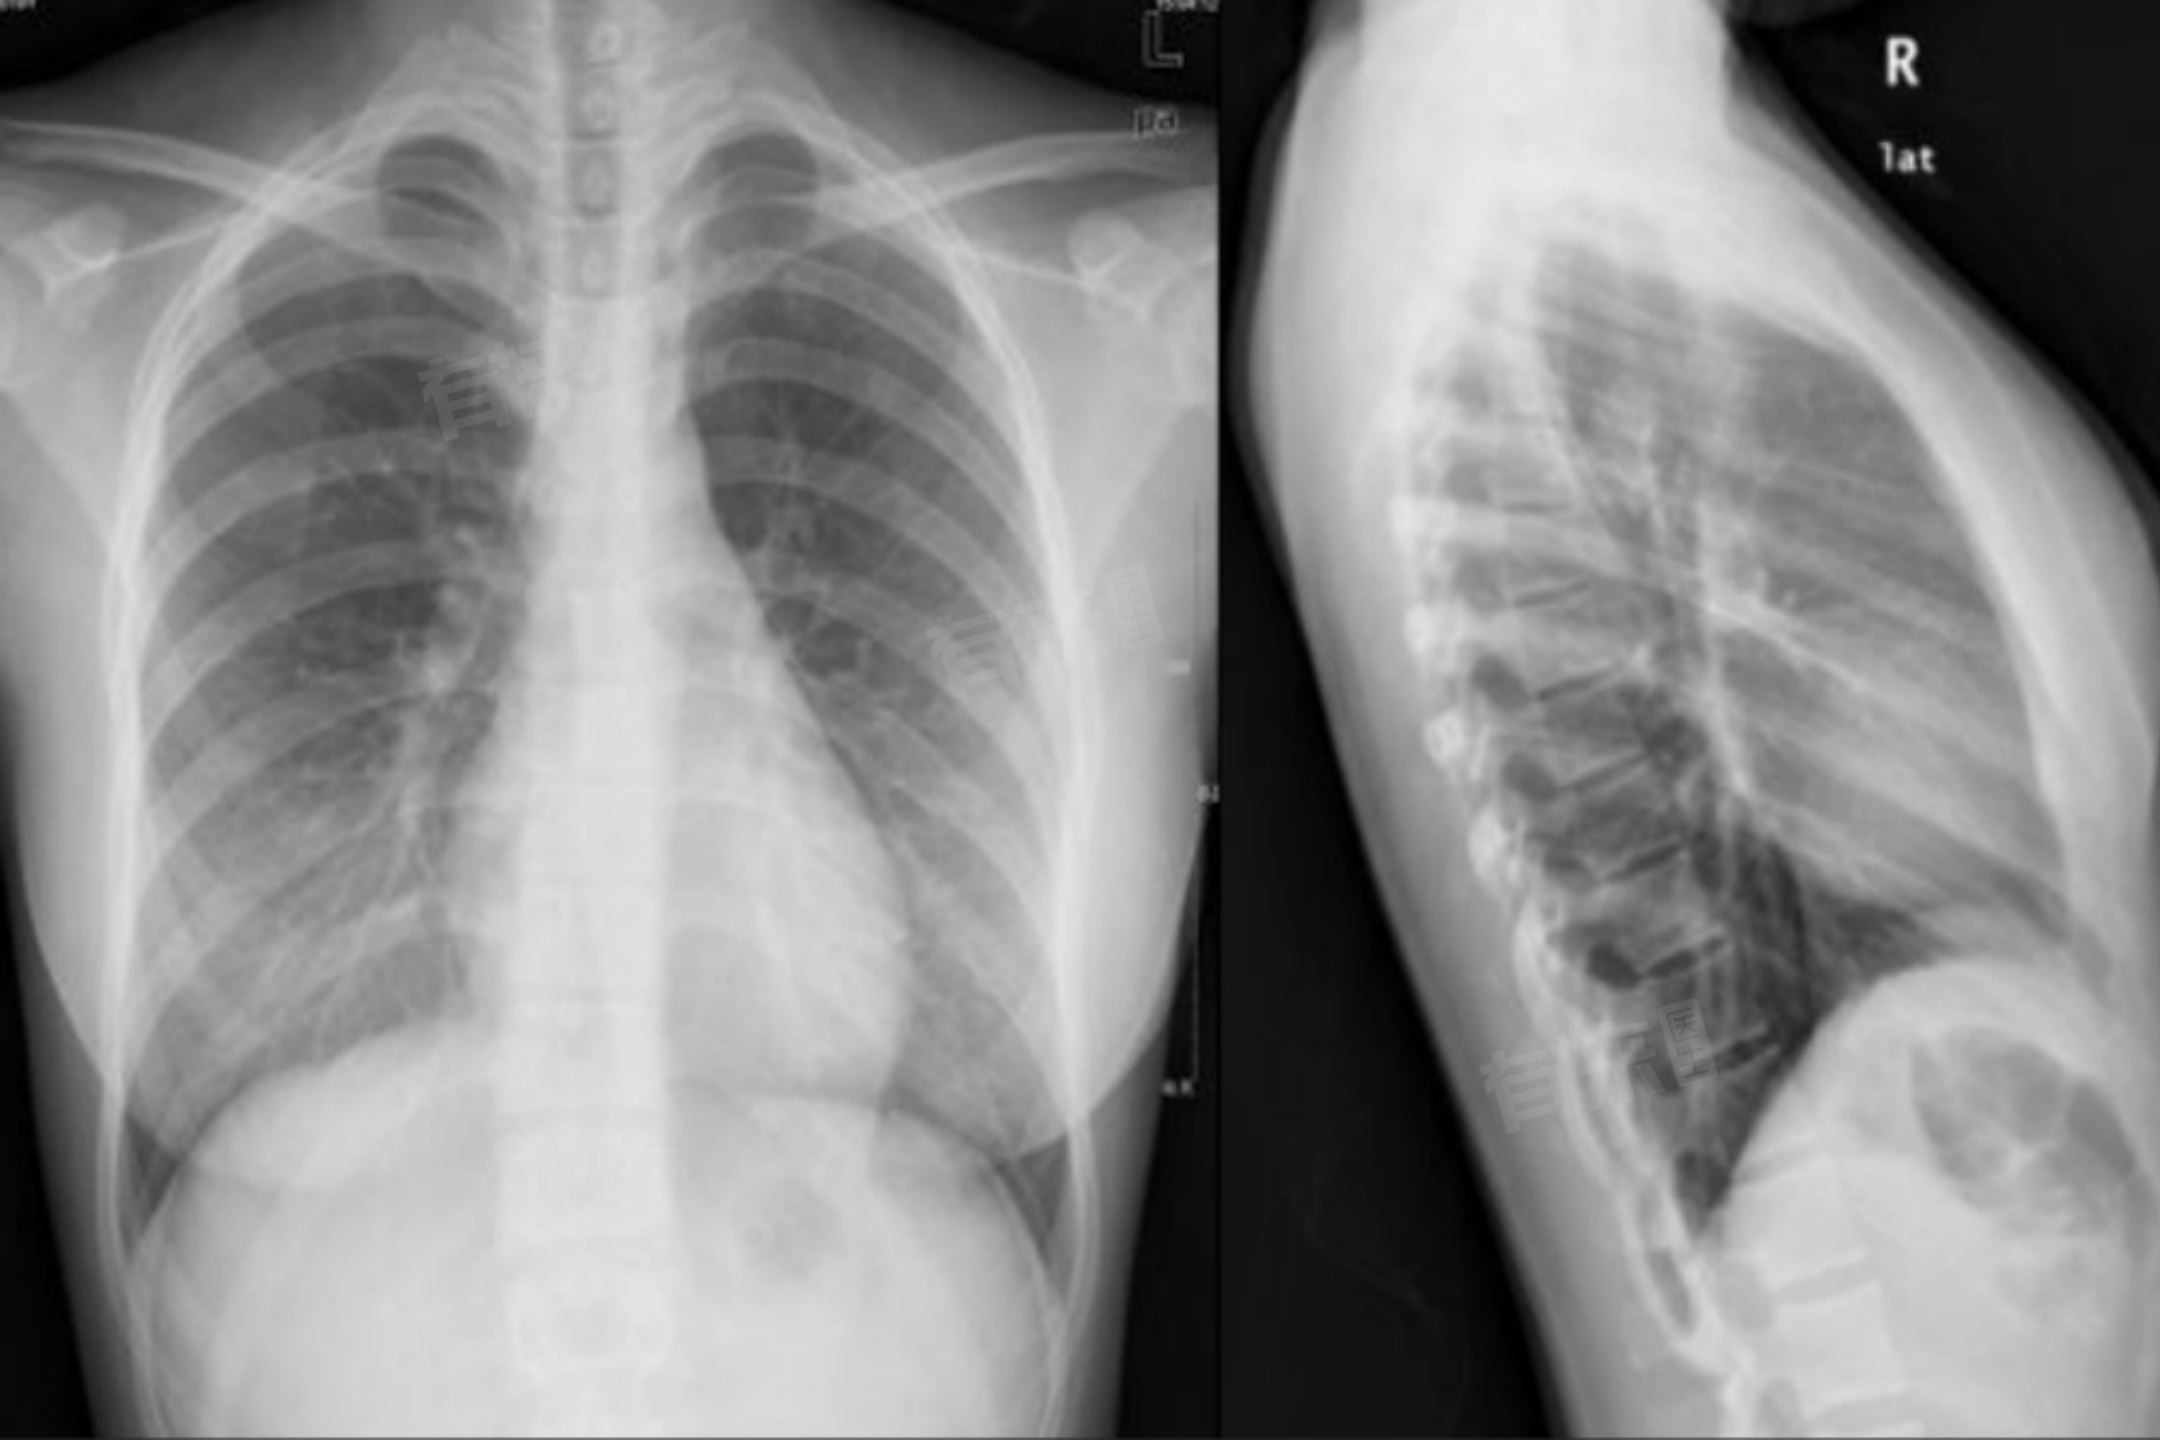

- DR则是数字化的X射线静态成像,一次曝光即可获取清晰的胸部图像,能清晰显示肺部纹理、肋骨等结构,对肺部小结节、轻微的骨折等病变有较好的检出能力,辐射剂量较胸透有所降低。